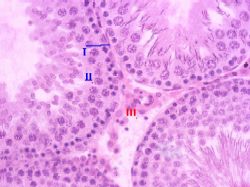

| Интер- стиций и его состав | Между канальцаминаходится рыхлая соединительная ткань - интерстиций (III),- а в её составе:

сосуды – кровеносные и лимфатические,

обычные соединительнотканные элементы и

интерстициальные клетки (клетки Лейдига, или гландулоциты), продуцирующие мужские половые гормоны (тестостерон и его производные).

| Роль лимфати- ческих сосудов | При этом, по современным представлениям,

каждый семенной каналец почти целиком окружён лимфатическим синусоидным капилляром (т.н. лимфатическим “чехликом ”, или “футляром”),

а мужские половые гормоны, в отличие от всех прочих гормонов, попадают вначале не в кровеносное, а в лимфатическое русло.